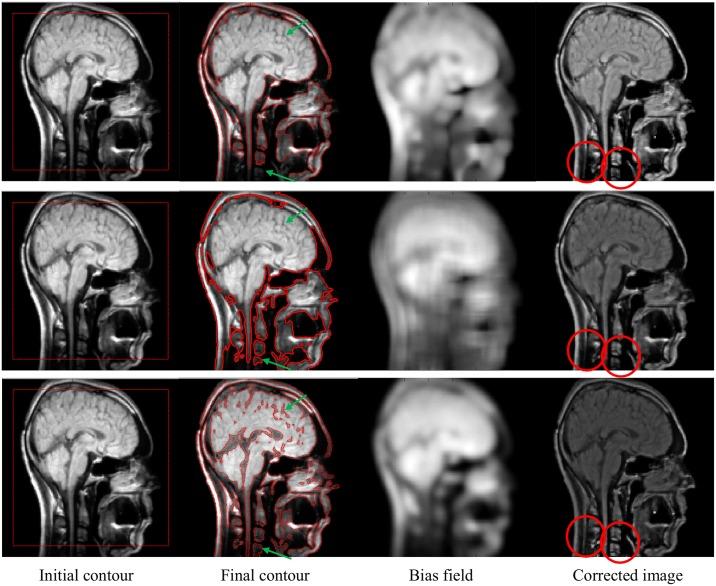

This paper presents a region-based active contour method for the segmentation of intensity inhomogeneous images using an energy functional based on local and global fitted images. A square image fitted model is defined by using both local and global fitted differences. Moreover, local and global signed pressure force functions are introduced in the solution of the energy functional to stabilize the gradient descent flow. In the final gradient descent solution, the local fitted term helps extract regions with intensity inhomogeneity, whereas the global fitted term targets homogeneous regions. A Gaussian kernel is applied to regularize the contour at each step, which not only smoothes it but also avoids the computationally expensive re-initialization. Intensity inhomogeneous images contain undesired smooth intensity variations (bias field) that alter the results of intensity-based segmentation methods. The bias field is approximated with a Gaussian distribution and the bias of intensity inhomogeneous regions is corrected by dividing the original image by the approximated bias field. In this paper, a two-phase model is first derived and then extended to a four-phase model to segment brain magnetic resonance (MR) images into the desired regions of interest. Experimental results with both synthetic and real brain MR images are used for a quantitative and qualitative comparison with state-of-the-art active contour methods to show the advantages of the proposed segmentation technique in practical terms.

本文提出了一种基于区域的主动轮廓方法,用于分割强度不均匀的图像,该方法使用基于局部和全局拟合图像的能量泛函。通过使用局部和全局拟合差异来定义方形图像拟合模型。此外,在能量泛函的求解中引入局部和全局符号压力力函数,以稳定梯度下降流。在最终的梯度下降解中,局部拟合项有助于提取具有强度不均匀性的区域,而全局拟合项针对均匀区域。在每一步应用高斯核来正则化轮廓,这不仅使其平滑,还避免了计算成本高昂的重新初始化。强度不均匀的图像包含不期望的平滑强度变化(偏差场),这会改变基于强度的分割方法的结果。偏差场用高斯分布近似,通过将原始图像除以近似偏差场来校正强度不均匀区域的偏差。本文首先推导了一个两相模型,然后将其扩展为四相模型,以将脑磁共振(MR)图像分割成所需的感兴趣区域。使用合成和真实脑MR图像的实验结果与现有最先进的主动轮廓方法进行定量和定性比较,以从实际角度展示所提出的分割技术的优势。